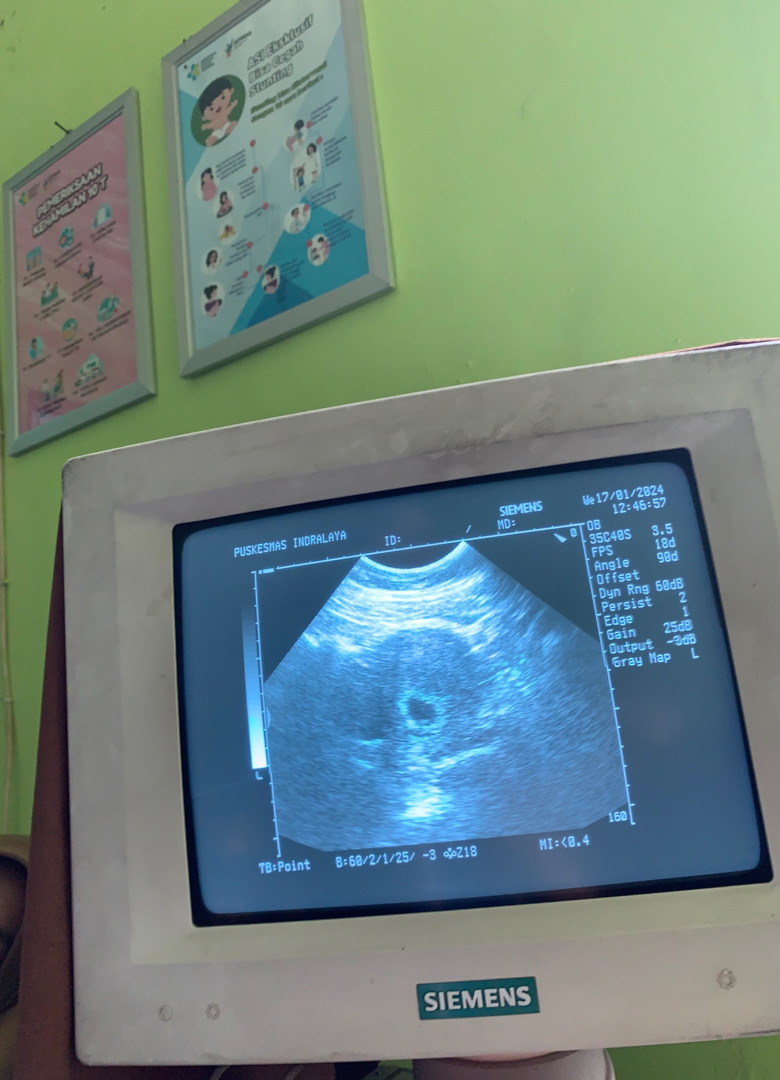

Bun sya usg di puskesmas tgl 17-01-2024 dibilang dokter udah 12weeks berarti 3 bulan, tapi pas bulan lalu tgl 27-12-2023 masih penebalan dinding rahim dan dokter bilang itu mungkin masih kisaran 4-5 minggu, yg benar yg mana bun ya, dan itu hasil usg di puskes

Itu foto usg tgl 17-01-2024 bun? Kalo liat dari hasil usg nya sih itu kaya masih 5-6minggu bun..kalo penebalan dinding rahim belum ada kantongnya..itu hasil usgnya baru kantong aja bun..kalo 12weeks sudah ada janinnya dan biasanya sudah lumayan panjang janinnya sudah bisa di cek CRL..coba usg ke dokter kandungan aja bun biar lebih pasti, soalnya hasil usg di trimester 1 yang jadi patokan hari tafsiran lahir, jangan kelewat..

Klo menurut HPHT udh 16 minggu an bun,aku aja HPHT 17_10_2023 kmren terakhir usg tgl 16_01_2024 udh 14 minggu,klo menurut hitungan ku mundur 1 minggu dr HPHT usg yg kmren ,iya itu kaya baru kantung nya aja ,seharus nya 12 minggu kantong janin udh besar dan janin udah kliatan nampak jelas